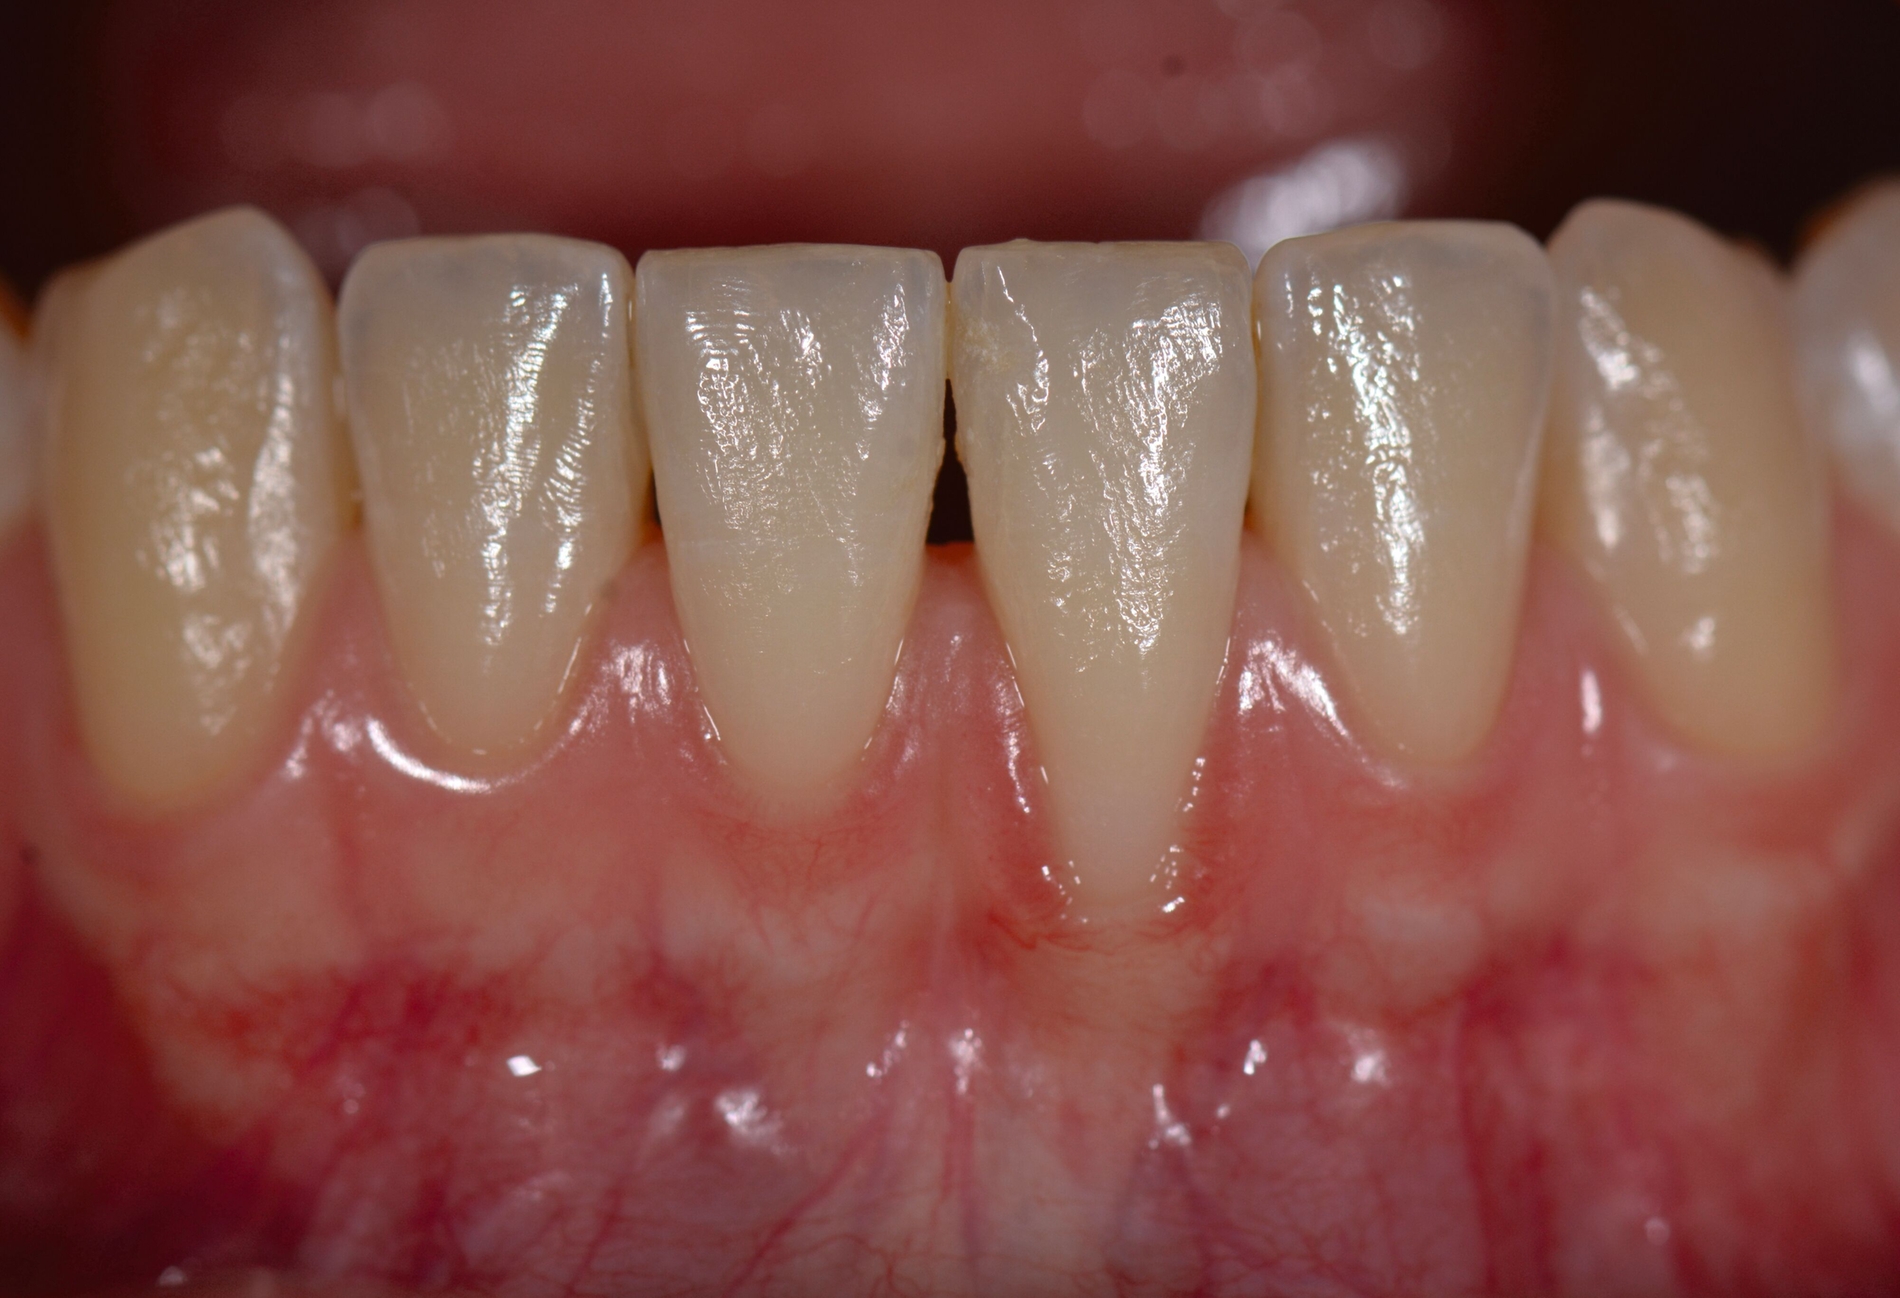

Das „klassische“ BGT wurde bereits in den 1970er-Jahren beschrieben und ist besonders verbreitet bei der Behandlung von gingivalen Rezessionen und der Weichgewebsaugmentation um Implantate. Das Transplantat wird durch eine sorgfältige Präparation unterhalb des Epithels vom lateralen und eher anterioren Gaumen gewonnen. Durch den Erhalt des bedeckenden Gewebes soll eine primäre Heilung sichergestellt werden. Die Höhe des Gaumendachs und somit die Entfernung zur Arteria palatina sowie die Dicke der Schleimhaut, vor allem über den palatinalen Wurzeln der Molaren zusammen mit den Rugae des anterioren Gaumens, sind die limitierenden Faktoren bei dieser Technik.

Trotz des Verbleibs des Epithels kann es zu sekundärer Wundheilung mit entsprechender Morbidität postoperativ kommen, besonders bei Techniken, die mehrere Inzisionen beinhalten, wie den sogenannten Trap-Door-Techniken, so dass sich die „Single-Incision-Technik“ durchgesetzt hat [Fickl et al., 2014]. Gegen eine übermäßige Blutung und postoperative Morbidität empfiehlt sich klinisch die routinemäßige Anwendung einer Verbandplatte, entweder in der Tiefziehtechnik oder präoperativ mittels eines Thermoplasts, so dass sich früh ein stabiles Blutkoagel bildet und die Wundheilung an der Entnahmestelle ungestört ablaufen kann. Dadurch wird die Morbidität klinisch deutlich reduziert. Das sBGT zeigt ästhetisch sehr gute Ergebnisse mit Blick auf Oberflächenstruktur sowie Farbe und kann unter anderem im Rahmen der Envelope- oder Tunneltechnik oder auch über einer Extraktionsalveole bewusst exponiert belassen werden, um zusätzlich befestigte Gingiva zu gewinnen.